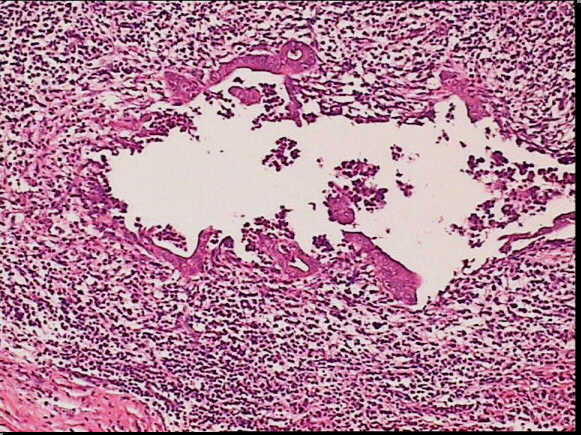

High-power view of the same slide shows the heavy inflammatory infiltrate in the epithelium layer with erosion and duct distorsion.